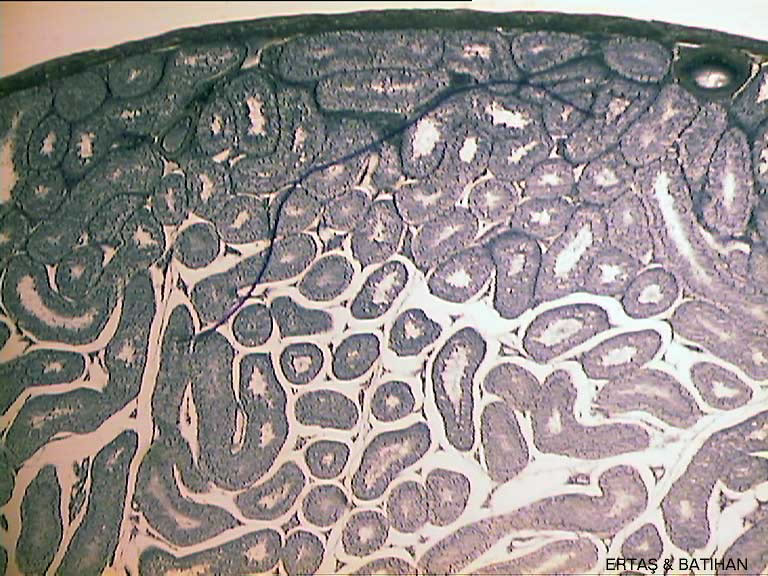

ı/Spermary-sec-1-(4)-(Testis).jpg